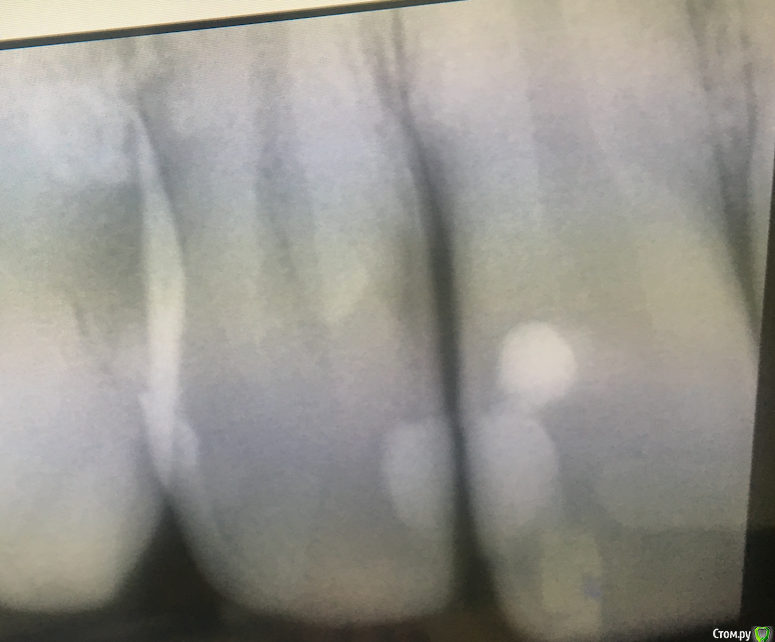

michaelks7 Опубликовано 2 февраля, 2019 Поделиться Опубликовано 2 февраля, 2019 Добрый день Предыстория: 14 числа было сложное удаление нижней 8ки10 дней антибиотиков + ~ 12 дней обезбаливающих ( с понижением силы/дозировок) Несколько дней назад после мороза хлебнул горячеватый кофе - заныл передний резец или около негоплюс на нижней челюсти периодически появляются ноющие ощущения в области 11-12 зубов(параллельно верхним с пломбами) - они ни разу не лечились - без пломбоколо них воспалена деснав моей бывшей клинике даже снимка не сделали - ограничились внешним осмотром, сказали чувствительность зубовв другой клинике посмотрели панорамный , также сделали прицельный. Вердикт , кариес под пломбами между зубов -перелечиватьпро нижние сказали все нормально, снимок делали, на нем тоже криминала не увидели. Сказали проблема скорее всего в зубном камне под деснойплюс под перелечивание отправили нижние правую 7 и левую 6 не могли бы вы взглянуть насколько все так как сказали или потенциальных проблем больше/меньше - появился вопрос с выбором стоматолога. В старую клинику не хочу возвращаться.и неясный момент с нижними 11-12 прикладываю панорамный снимок и прицельный передних с пломбамиЗаранее спасибо Ссылка на комментарий

michaelks7 Опубликовано 4 февраля, 2019 Автор Поделиться Опубликовано 4 февраля, 2019 добрый день0 откликоввзгляните пожалуйста , основные жалобы 21-22 зуб несколько дней назад была разовая реакция на температуру. после этого периодически появляются слабые ноющие ощущения. вторичный кариес может такое вызывать или грешить сразу на пульпит?про перелечивание зубов 16/17/26/27/36/37 , какие из них на ваш взгляд требуют повторного лечения?спасибо, надеюсь на получение ответа Ссылка на комментарий

red_butler Опубликовано 4 февраля, 2019 Поделиться Опубликовано 4 февраля, 2019 на снимках кариеса не увидел, покажите фото зубов Ссылка на комментарий